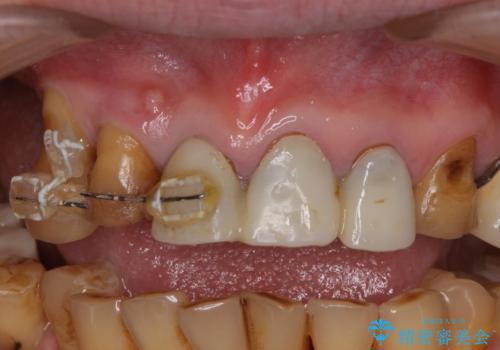

- 前歯の部分矯正や仮歯に置き換えるなど、治療途中のまま放置してしまったとのことで来院された患者様です。

骨格的に下顎骨が前方にあり、歯列の幅も下顎の方が大きいため、奥歯に負担のかかりやすい咬合でした。

前歯部については抜歯が必要な歯を抜歯し、インプラントやブリッジなどにより補綴治療を行うこととしました。